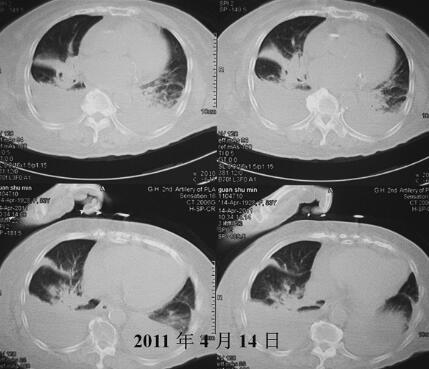

诊治经过:入院时将患者由平车搬至病床时,患者突发严重呼吸困难,大汗,双肺广泛哮鸣音,心电监护示HR 132次/分,BP 148/74mmHg,指氧饱和度(吸氧浓度33%)90%。血气分析(吸氧浓度33%):pH 7.33,PO2 69mmHg,PCO2 46mmHg,HCO3− 23.6mmol/L,BE −1.9mmol/L。考虑突发急性左心衰竭,给予地塞米松10mg静推,毛花苷丙0.4g缓慢静推,特布他林0.25mg缓慢静滴及无创呼吸机辅助通气(模式ST参数:IPAP 16cmH2O,EPAP 6cmH2O,2次/分),约30分钟后呼吸困难缓解,心率降至99次/分。入院后查胸部CT(图3、图4):右侧中下肺片状影,双侧胸腔积液,二尖瓣、主动脉、冠状动脉钙化斑。给予莫西沙星抗感染、多索茶碱+特布他林平喘、氨溴索祛痰、灯盏花素+单硝酸异山梨酯扩张冠状动脉、改善微循环、右侧胸腔闭式引流等治疗。胸腔积液常规:淡黄色,透明,李凡他试验阴性,细胞总数110×106/L,白细胞26×106/L,淋巴细胞74%;ADA 3.10U/L。胸腔积液生化:总蛋白15.1g/L,LDH 96.40U/L,Glu 8.20mmol/L。胸腔积液性质为漏出性,考虑心力衰竭导致。经过治疗,病情明显改善,15日07:05复查血气分析(吸氧浓度33%):pH 7.400,PO2 112mmHg,PCO2 39mmHg, 23.7mmol/L,BE −0.5mmol/L。之后患者喂食时出现呛咳后再次突发喘憋,听诊双肺满布痰鸣音及喘鸣音,立即给予吸痰,吸出大量牛奶及食物残渣,查血气分析(吸氧浓度33%):pH 7.32,PO2 44mmHg,PCO2 59mmHg, 22mmol/L,BE −3.2mmol/L。给予氢化可得松琥珀酸钠200mg静滴,以解痉、平喘、抗过敏,约15分钟后患者症状好转。给予留置胃管,行鼻饲进食。经过加用激素(16、17日氢化可得松琥珀酸钠100mg,18、19日氢化可得松琥珀酸钠50mg)、强心(地高辛0.25mg,每日1次)治疗4日,患者病情逐渐好转,咳嗽、喘憋明显减轻,咳痰减少。但患者之后仍因反复误吸、感染和反复缺氧导致病情逐渐加重,进而心肌损害、心功能不全也进一步加重。继续给予抗感染、强心、碳酸氢钠纠正酸中毒、左侧胸腔闭式引流、间断无创呼吸机辅助通气等进一步治疗3日,病情仍有反复(图5)。患者家属要求放弃气管插管等有创抢救措施,于4月24日14:00患者心率、血压突发下降,经抢救无效,于24日14:37死亡。

图3 入院后胸部X线CT(肿瘤)

图4 入院后胸部CT(纵隔瘤)